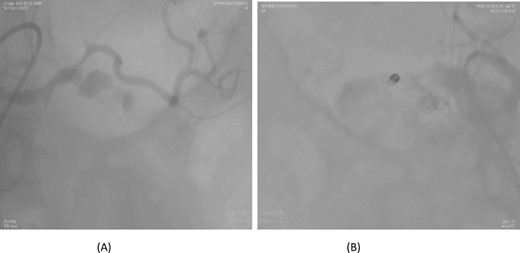

A 36-year-old female underwent a Whipple’s pancreaticoduodenectomy for pancreatic adenocarcinoma. On the fifth postoperative day, she experienced massive upper gastrointestinal bleeding, confirmed by endoscopy showing massive clots. A contrast-enhanced CT angiogram revealed a pseudoaneurysm from the proper hepatic artery, with abrupt truncation of the left gastric artery. Angioembolization was performed, with coil embolization of the proper hepatic artery and super selective embolization of the left gastric artery using gel foam. However, 32 days later, the patient experienced re-bleeding. A follow-up CT angiogram showed dislodging of the coil in the proper hepatic artery, allowing contrast through the coil and into the pseudoaneurysm. A second angioembolization repositioned the coil and used 70% glue and Lipiodol for embolization. Post-procedure, the patient had no further complications and was stable at follow-up (Fig. 3).

Case 3. (A) Angiogram shows pseudoaneurysm from proper hepatic artery. (B) Angioembolization of proper hepatic artery with coil.